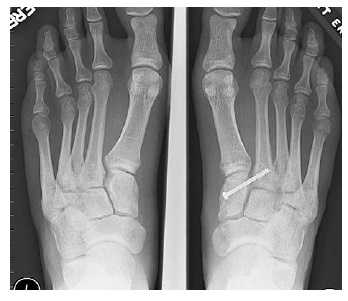

Рентгенография используется для определения угла между линиями, проведёнными между первой плюсневой костью и проксимальной фалангой первого пальца. Если угол больше 15°, подтверждает диагноз hallux valgus. Если угол составляет 45-50° — консервативное лечение не показано. Также должны быть определены степень смещения сесамовидных костей и уровень остеоартрита первого плюсне-фалангового сустава.

Если неоперативное лечение не помогло, необходимо рассмотреть вопрос о хирургическом лечении (уровень доказательности: 4). Перед выполнением операции необходимо определить степень тяжести hallux valgus. Для этого следует выполнить рентгенографию стоп в положении стоя.

Отдельно стоит разобрать тему разрыва связки Лисфранка с изолированной нестабильностью 2 предплюсне-плюсневого сустава. Частота данного повреждения значительно выросла за последние 50 лет в связи с популяризацией спорта. Также крайне высота частота отсроченной постановки диагноза. При этой патологии пациента беспокоит боль по тыльной поверхности 1-2-3 предплюсне-плюсневых суставов при физической нагрузке. Часто при осмотре удаётся обнаружить деформацию в данной области. Если осмотр производится отсрочено через несколько недель или месяцев после травмы то клинически определить нестабильность уже не удастся, однако на рентгенограммах с нагрузкой будет виден диастаз между медиальной клиновидной костью и основанием 2 плюсневой кости.

В случаях этого повреждения показано оперативное лечение, открытое устранение подвывиха основания 2 плюсневой кости с фиксацией винтом. Устранение подвывиха производится из доступа в 1 межплюсневом промежутке, рубцовая ткань и остатки связки могут интерпонировать сустав, тогда потребуется их удалить. После вправления производится предварительная фиксация спицей и рентгенологический контроль.

Затем устанавливается винт соединяющий основание 2 плюсневой кости и медиальную клиновидную кость.